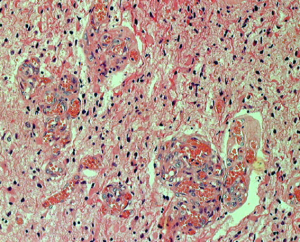

左に細かい石灰化が見られます。右は,グレード2の乏突起膠腫には珍しい血管内皮の増生 gromerulation なのですが,必ずしも悪性像とはいえません。通常の乏突起膠腫と同様にchicken wireと呼ばれるような細かい腫瘍血管網も存在しました。